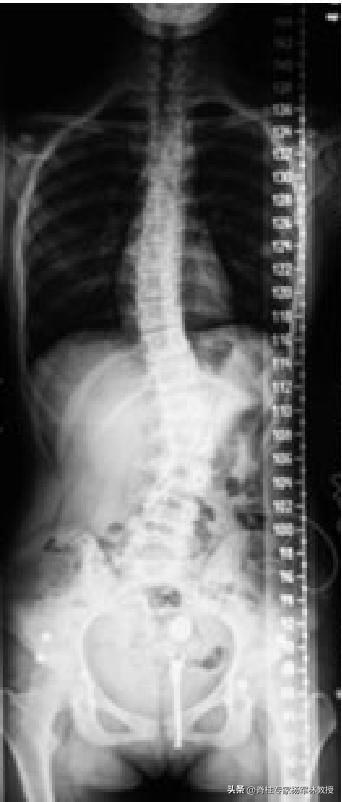

标准的全脊柱X光片是怎么样的?

正位片

侧位片

1、采取站立位。

2、包含下颈椎、双肩和双髋关节的全脊柱正位片和侧位片。